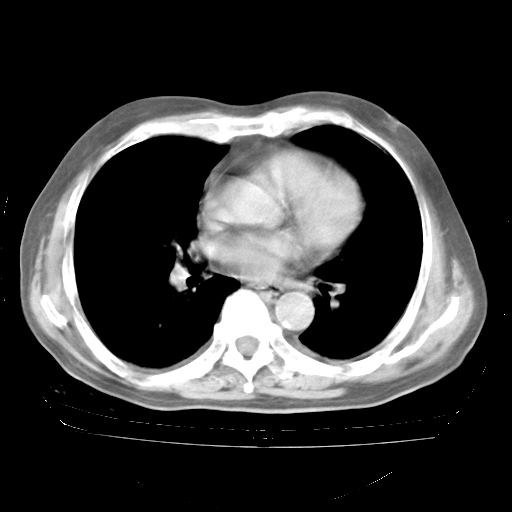

轻微咳嗽,无痰,(体温正常时)R20次/分,P75次/分,双肺底、腋下可闻及少量捻发音。下肢轻度浮肿。

ECG:右心室增大

心脏超声检查:无右心室增大。